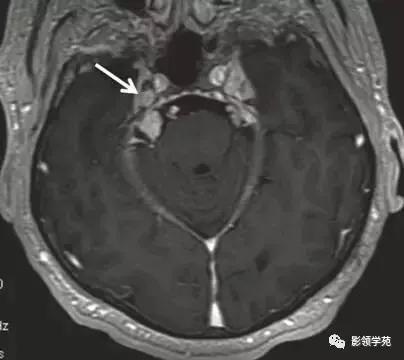

图 1 为神经纤维瘤病患者,注射钆造影剂后右侧桥小脑角内的迷走神经瘤成高信号